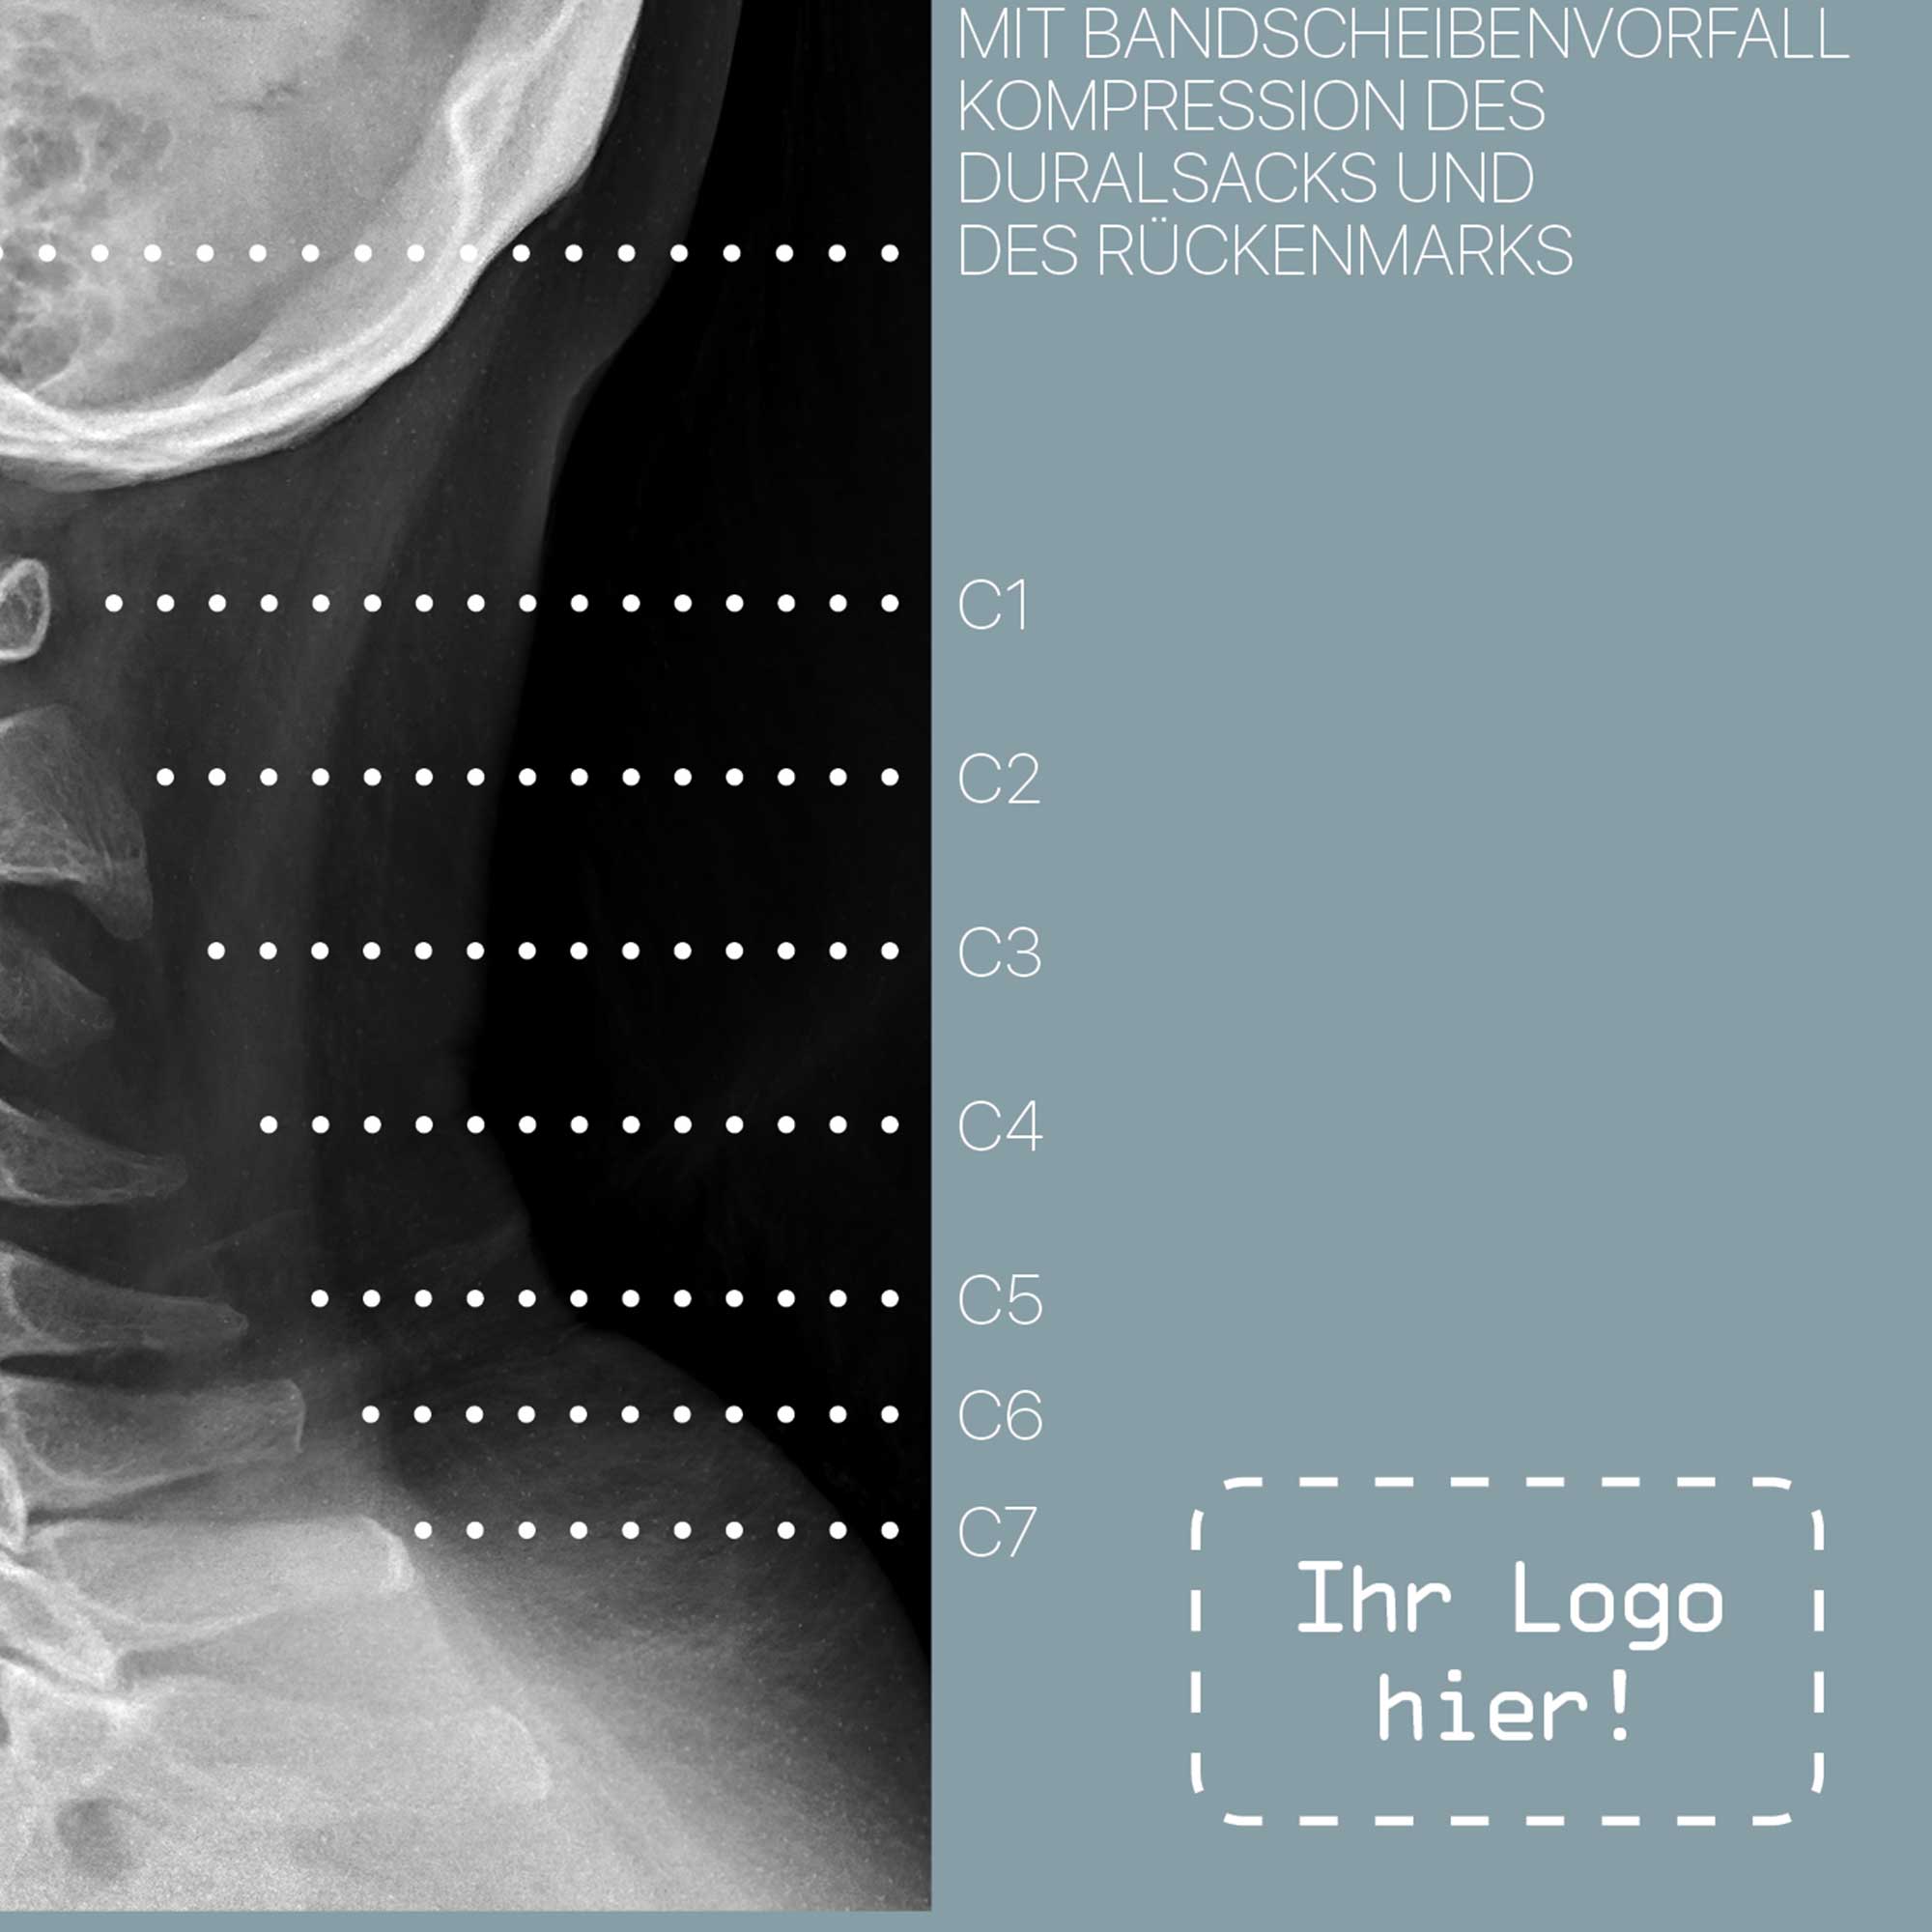

Zervikale Pathologie

fortschreitender Verfall

Wirbelsäule

Degeneration